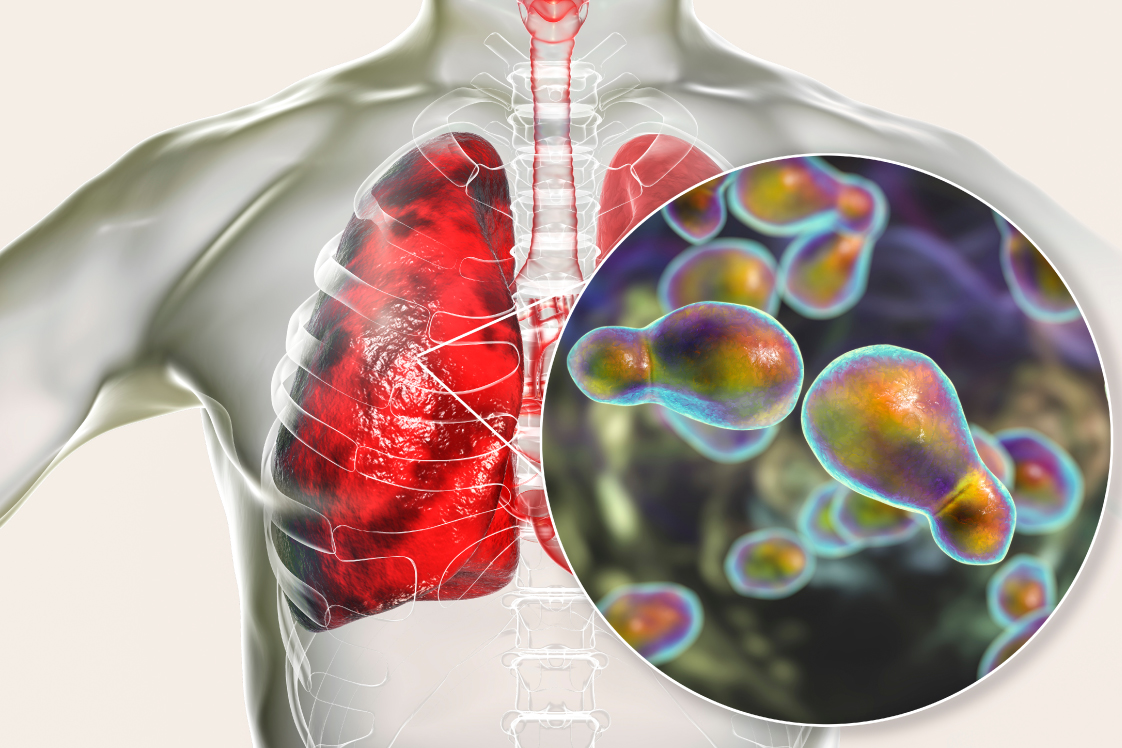

肺クリプトコックス症

肺クリプトコックス症は、主に土壌に生息するクリプトコックス・ネオフォルマンス(真菌の種類)によって引き起こされ、鳥類の糞を介して人間に感染するケースがあります。